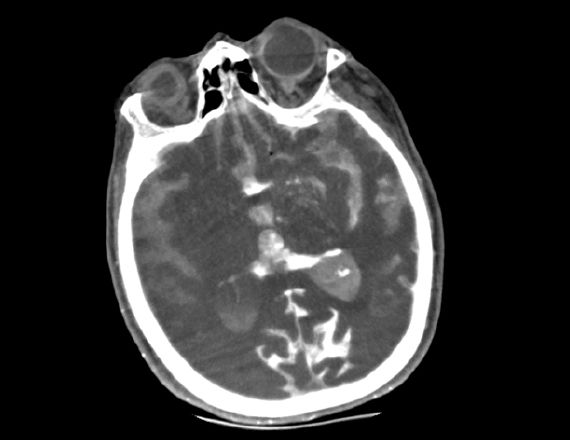

A patient with suspected TIA or stroke receives a general and neurological examination followed by diagnostic brain imaging, performed immediately on arrival so that treatment can be started promptly. 3 Optimal scanning coupled with workflow applications and protocols designed for stroke help deliver accurate and quick diagnosis to impact patient outcomes.

<p>Revolution brand of CT systems</p>

Read More

<p>FastStroke CT Application</p>

<p>Fast Brain protocol with HyperWorks</p>